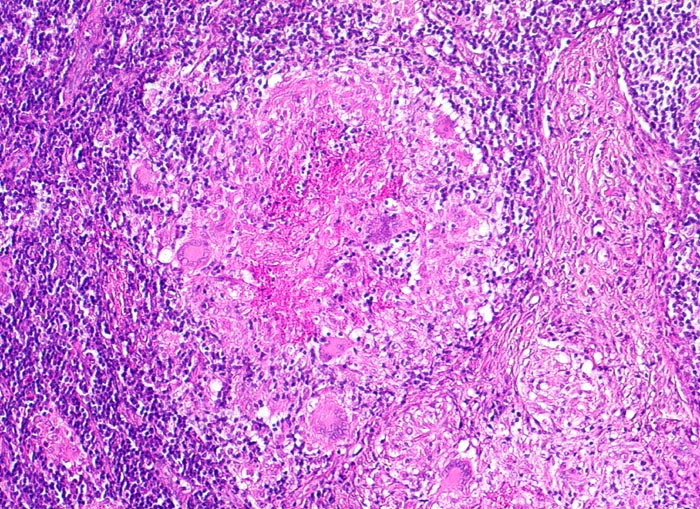

Morphologische Merkmale:

• Lymphknoten mit ausgedehnten konfluierenden eosinophilen Nekrosezonen und nur wenig erhaltenem Lymphknotengewebe (blau).

• In den grösseren Nekrosearealen sind Kerntrümmer von neutrophilen Granulozyten erkennbar.

• Demarkierung der Nekroseareale durch schlanke Epitheloidzellen, Riesenzellen vom Langhanstyp mit hufeisenförmig angeordneten Kernen und Lymphozyten.